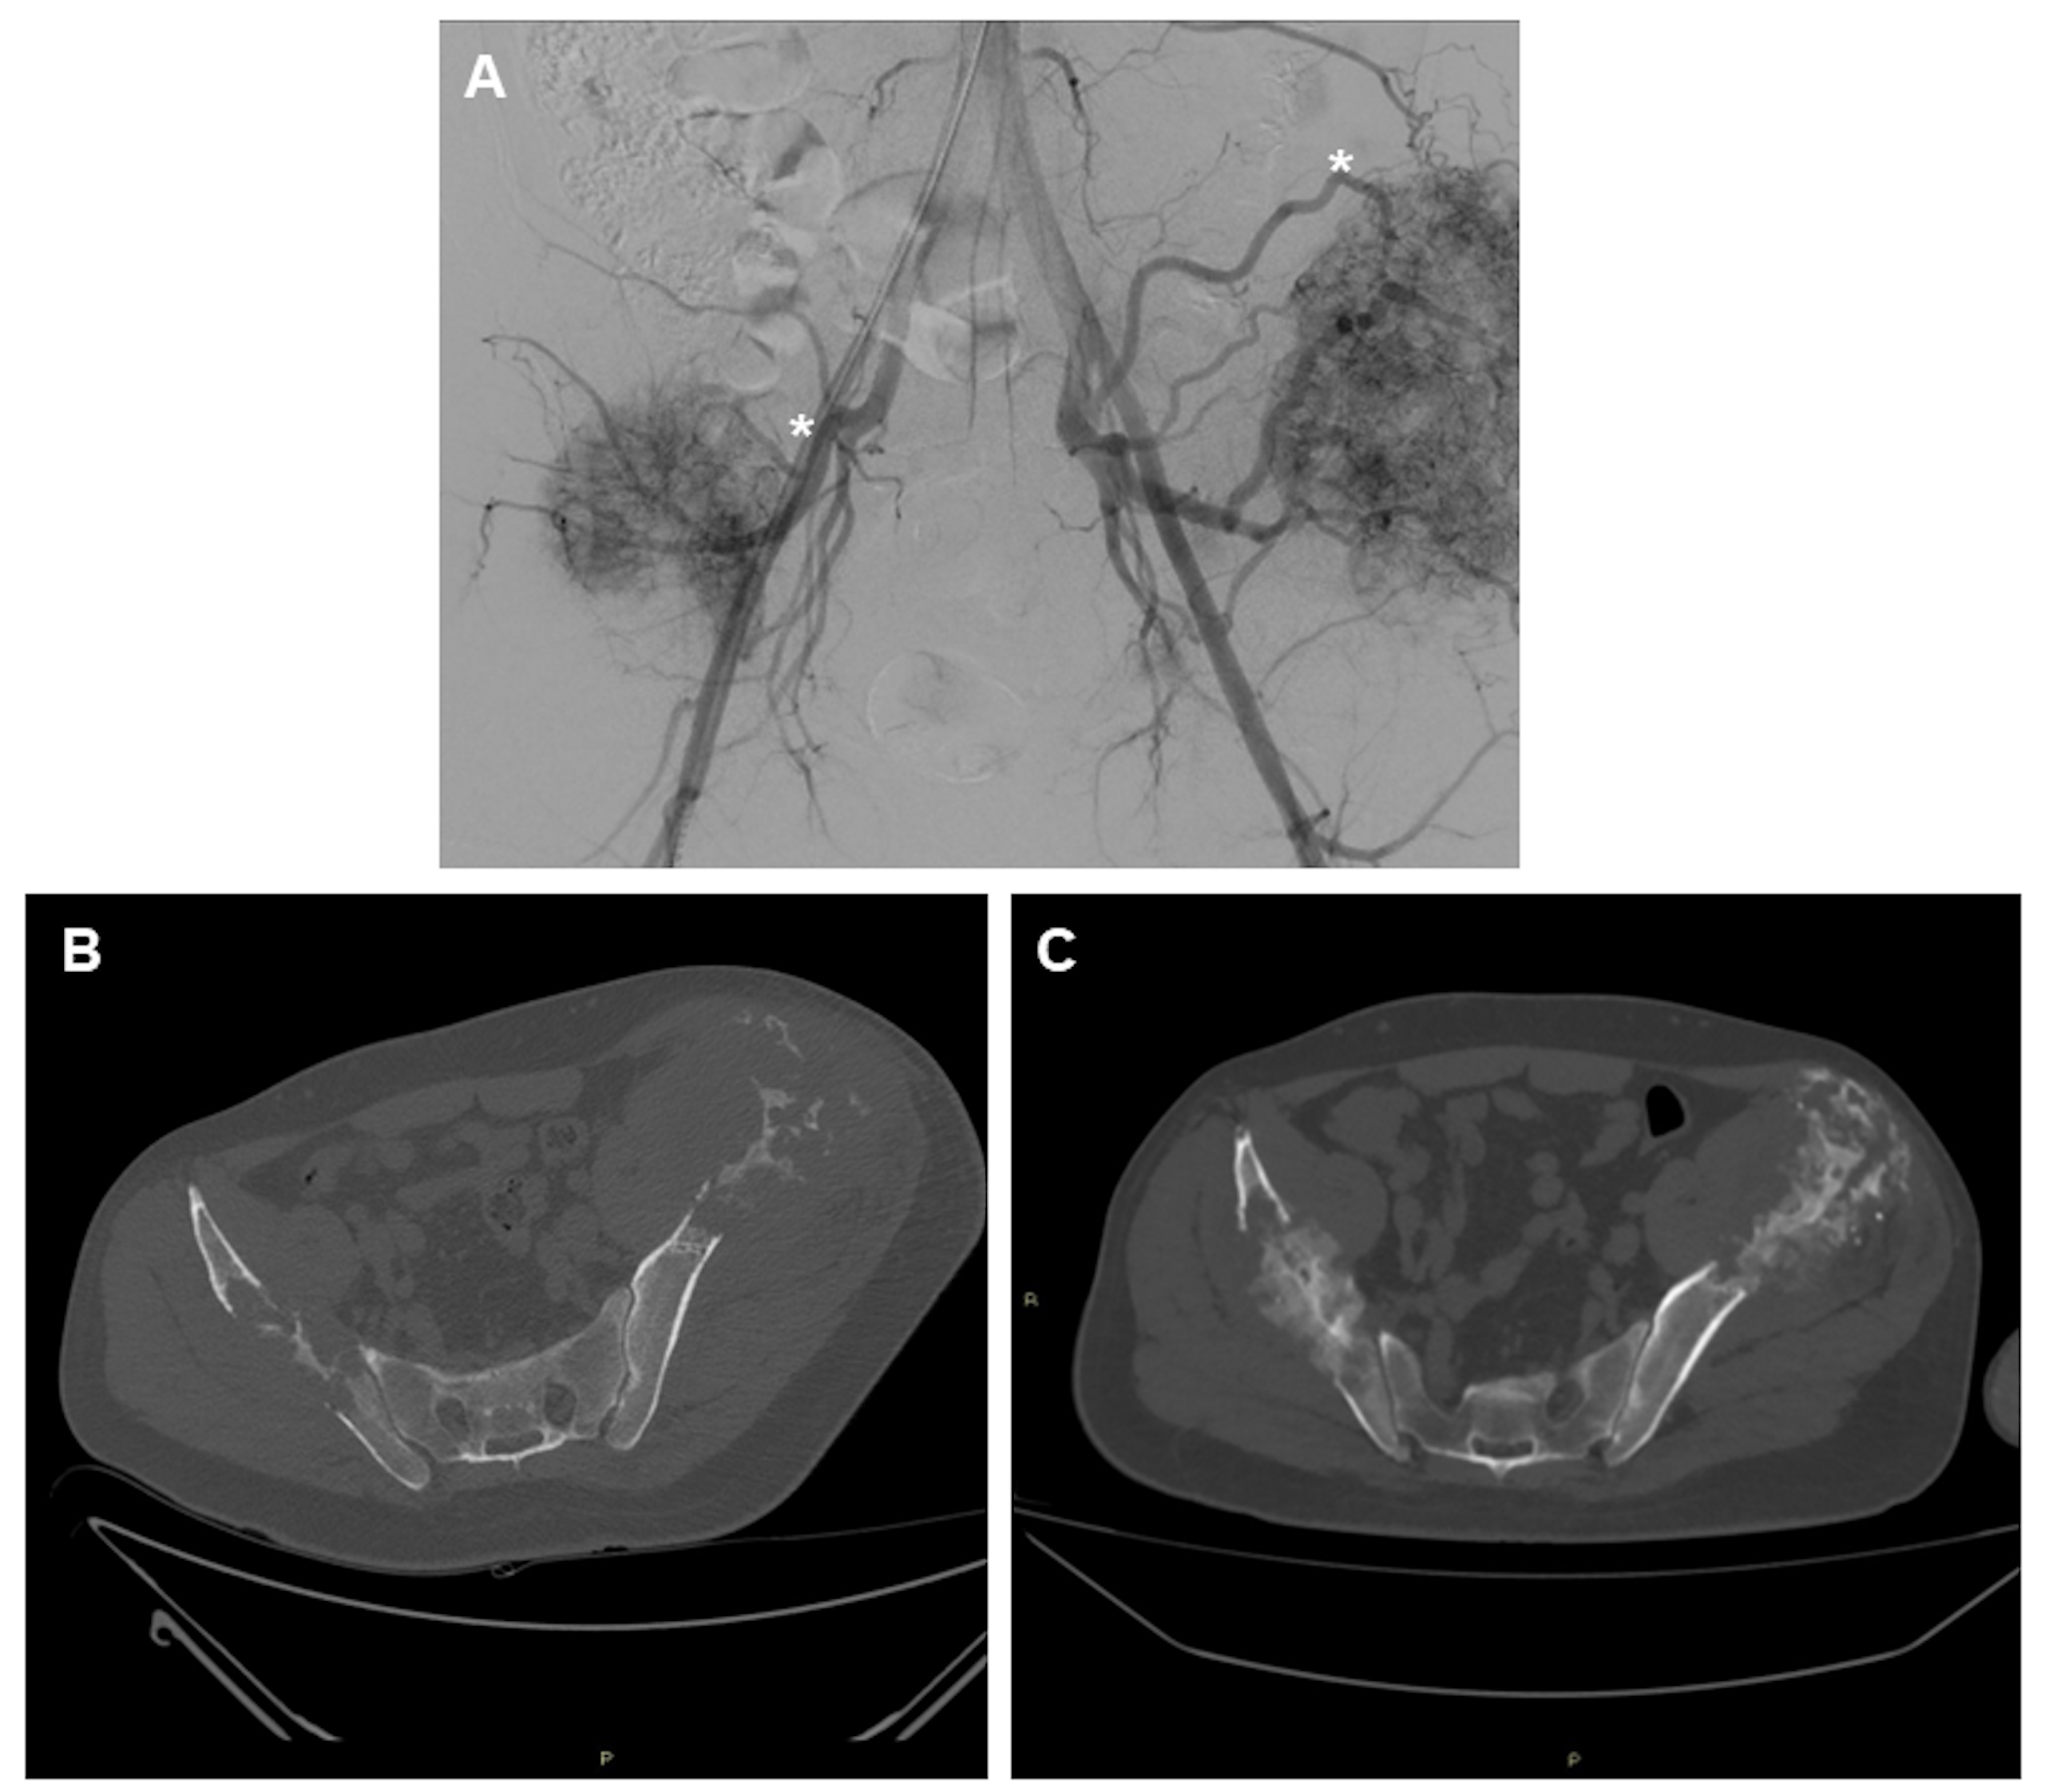

2.2. Preoperative Embolization

2.5. Challenging Locations